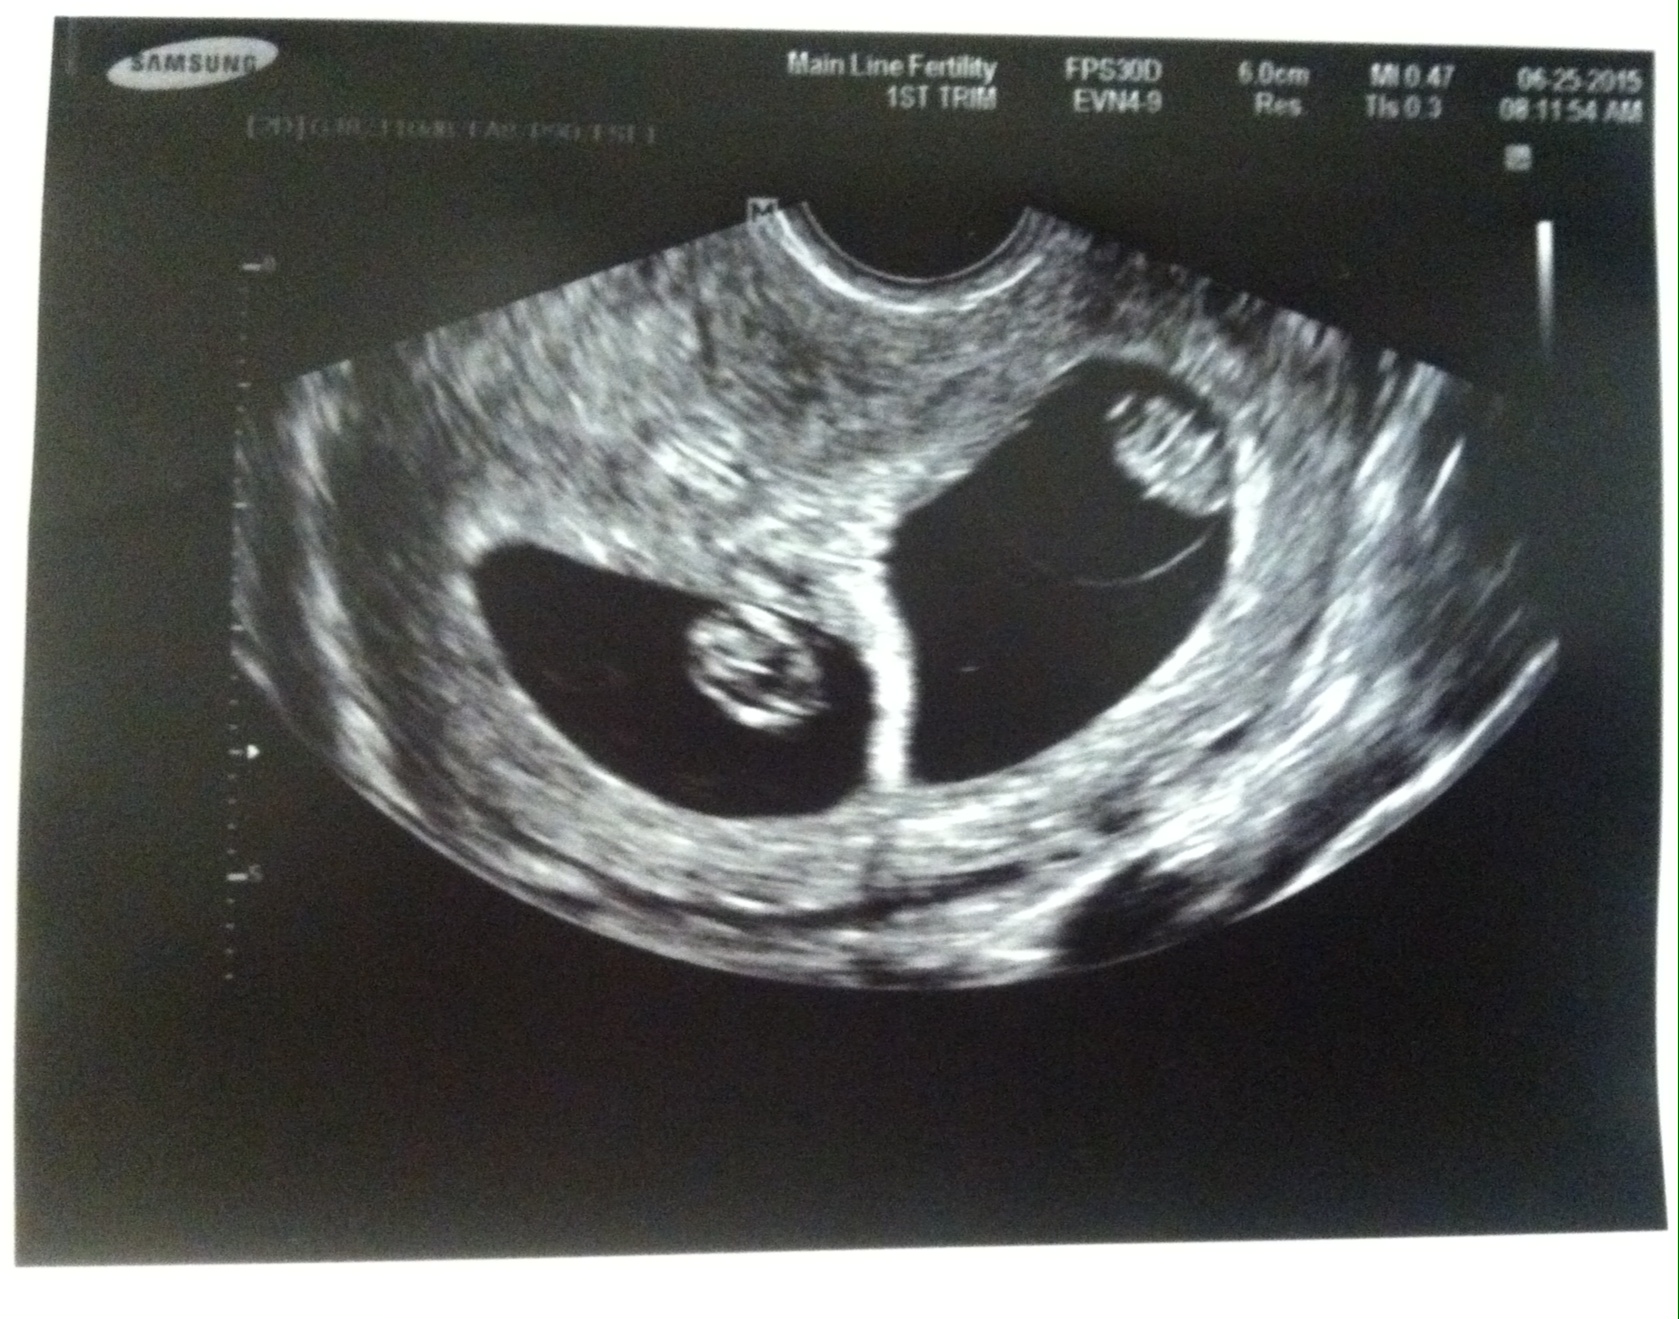

Mine is super hard to see, but what do you guys think? It was abdominal and the baby measured 8+6. Is that too late for this "theory"? I will get my blood test results in the next few weeks and am curious about whether they will align.

Is it the side the baby is on or the yolk sac or what? I read the placenta online, but I thought there wasn't placenta yet. My baby is kind of right in the middle but the yolk sac is definitely on the left.